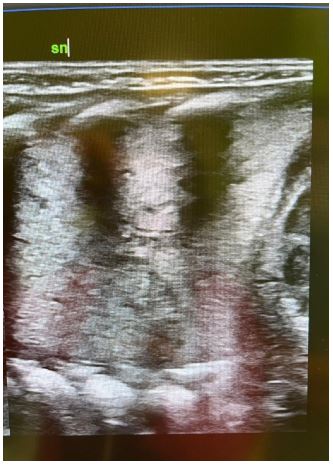

E.J. term newborn born by C-section due to maternal hypertension and obesity. At 6 hrs of life the newborn was referred to our NICU for transient neonatal tachypnoea needed nCPAP for at least 24 hrs with rapid improvement in respiratory dynamics and oxygenation. During the first days of life the patient developed feeding intolerance. Due to recurrent vomiting and familiar hystory of multicystic displasic kidney we perfomed abdominal ultrasound: no abdominal malformations were found but an incidental finding of bilateral pleural effusion was detected. Chest x Ray confirmed the minimal pleural effusion without other patological signs. To monitor lung parenchima, serial lung ultrasounds were performed. LUS revealed a progressive reduction in pleural effusion but surprisingly a portion of consolidation area in the left basal lobe, suspected for pulmonary sequestration, was detected (Figure 1).

Figure 1: LUS imaging: using a micro-linear ‘hockey-stick’ probe, in the left basal lobe is identified a portion of large consolidation area, suspected for pulmonary sequestration.